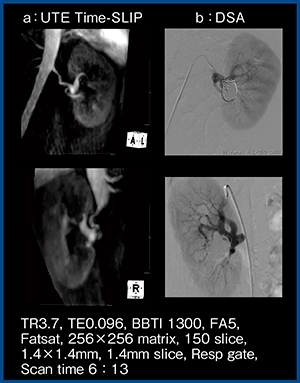

症例1は,左腎動脈瘤に対するコイル塞栓術後である。UTE Time-SLIP(図6 a)では磁化率アーチファクトの影響がほとんどなく,血管形状はDSA(図6 b)と同様であった。

図6 症例1:左腎動脈瘤コイル塞栓術後の |